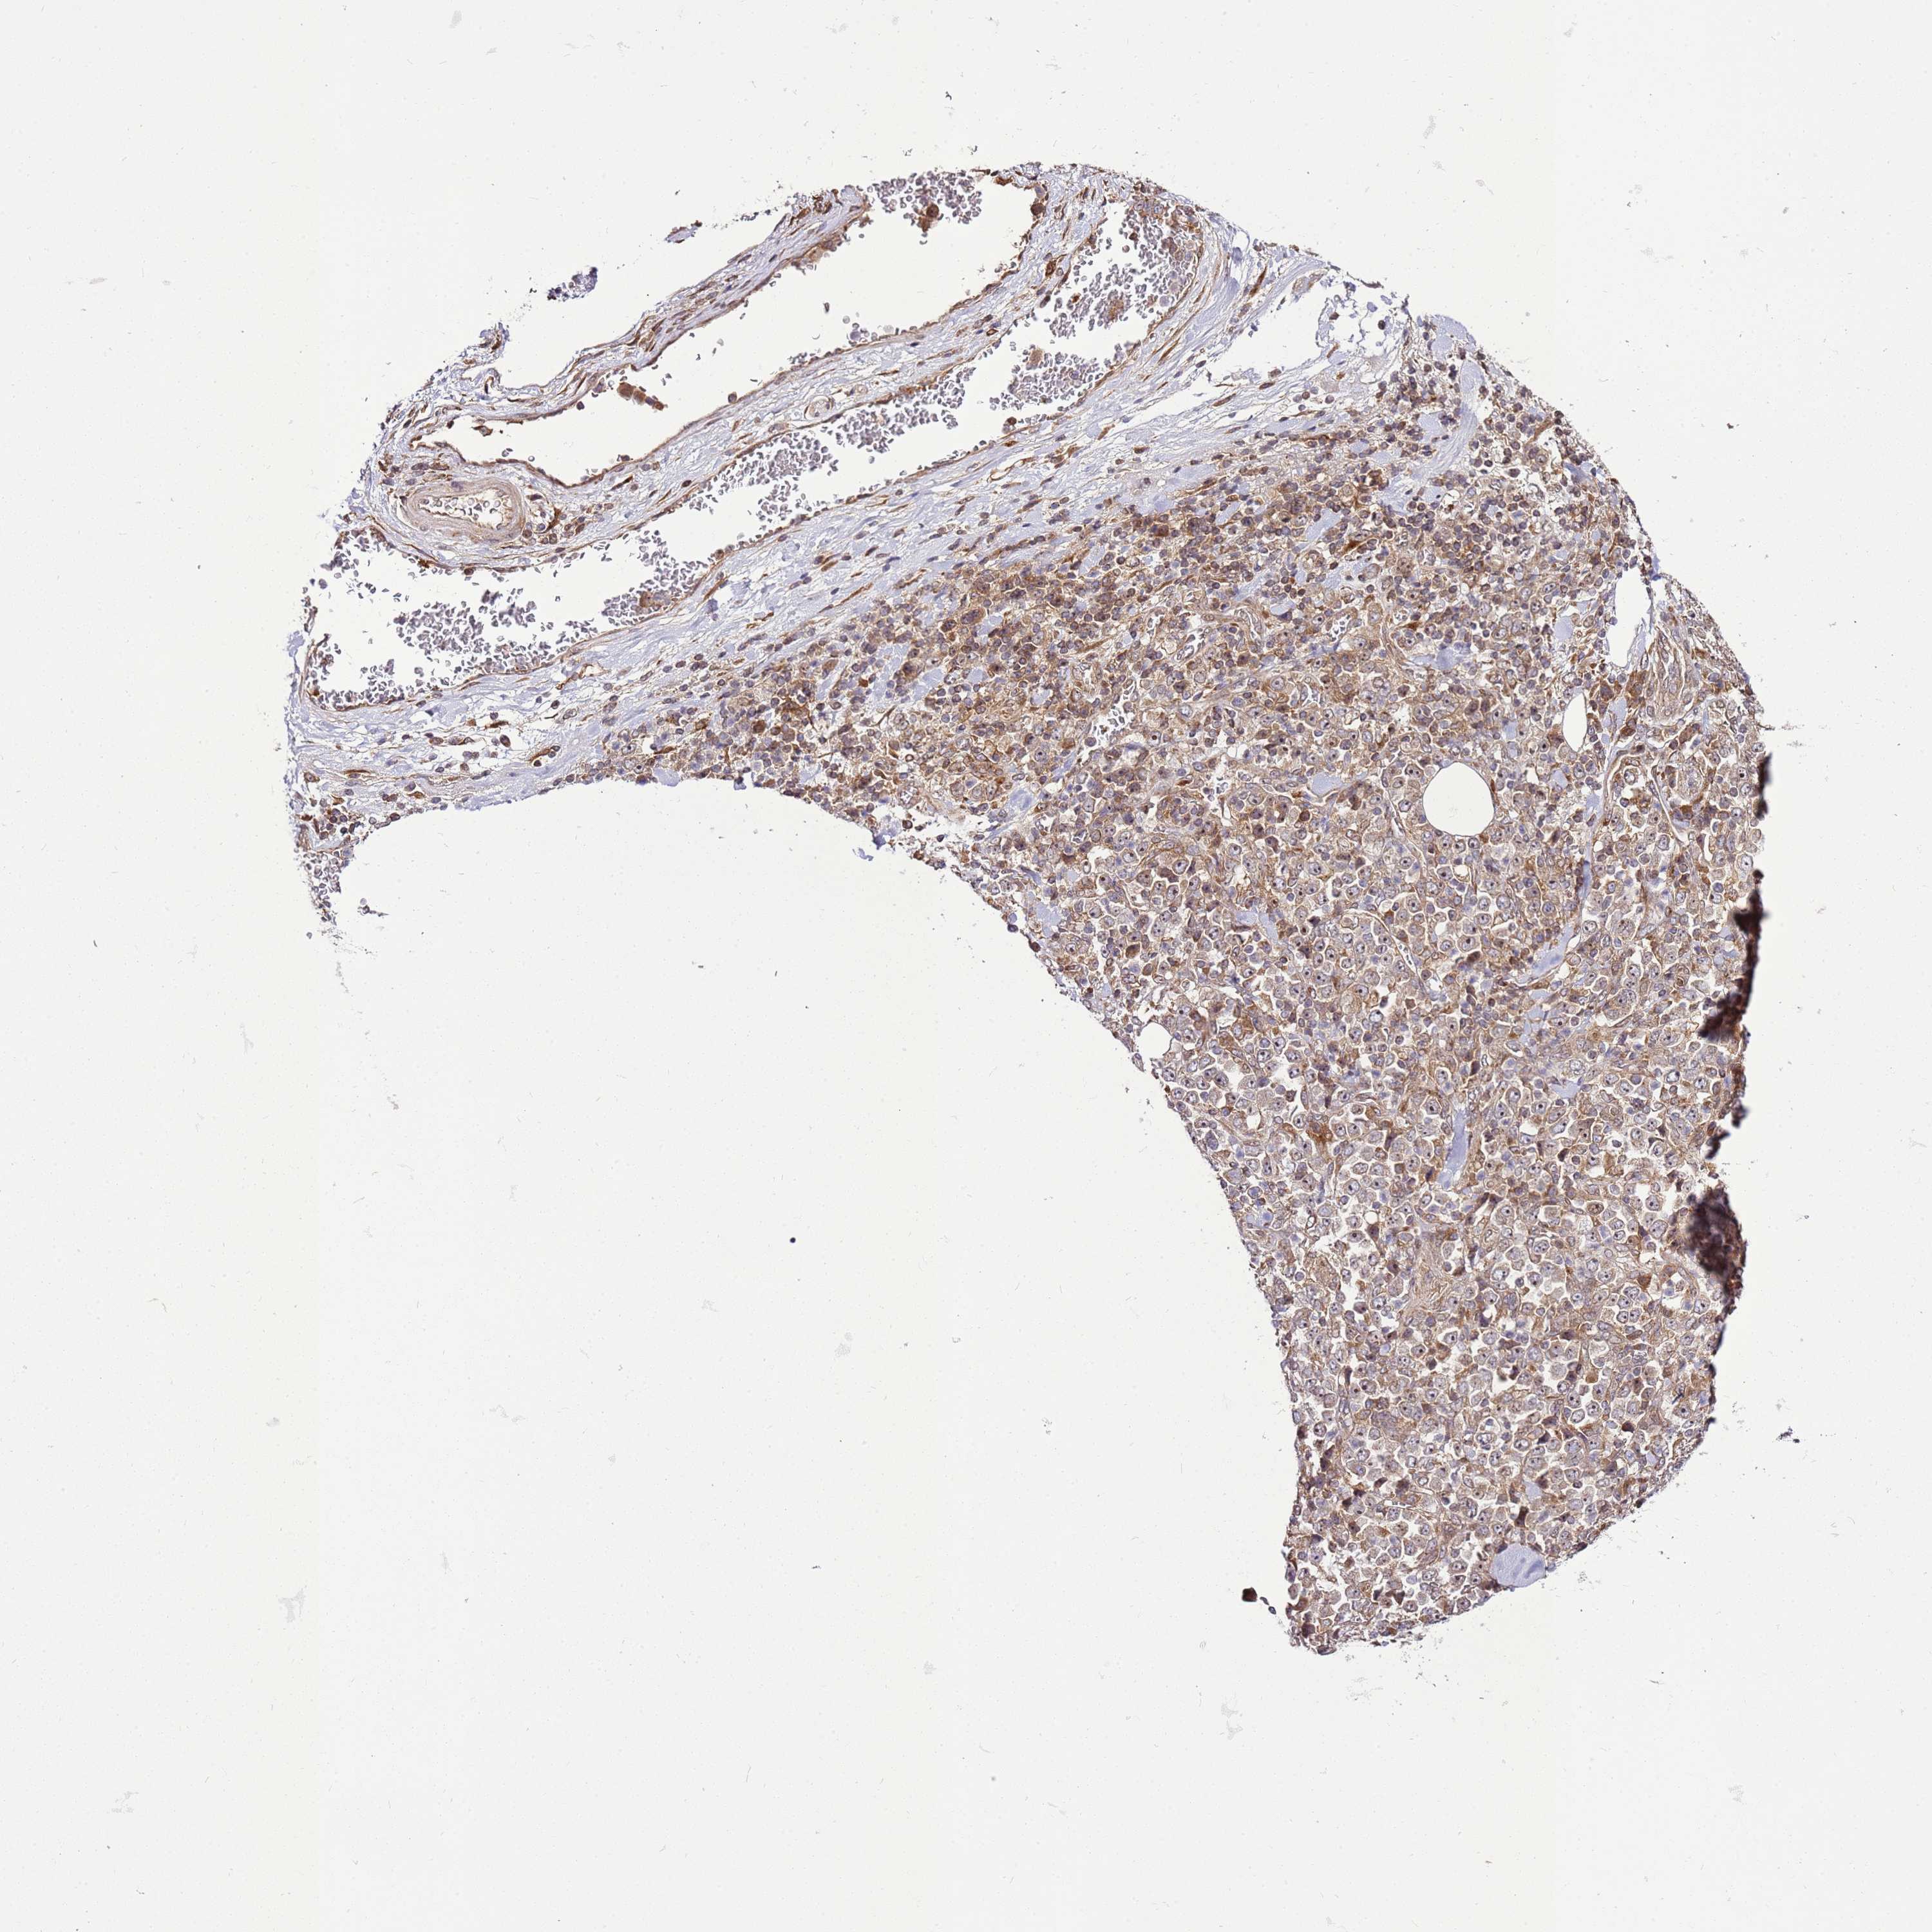

STOMACH CANCER - Protein expressioni

A mouse-over function shows sample information and annotation data. Click on an image to view it in a full screen mode. Samples can be filtered based on level of antibody staining by selecting one or several of the following categories: high, medium, low and not detected. The assay and annotation is described here.

Antibody stainingi

Antibody staining in the annotated cell types in the current human tissue is reported as not detected, low, medium, or high, based on conventional immunohistochemistry profiling in selected tissues. This score is based on the combination of the staining intensity and fraction of stained cells.

Each image is clickable and will lead to virtual microscopy that enables deeper exploration of all samples and also displays staining intensity scores, fraction scores and subcellular localization as well as patient and tissue information for each sample.

Antibody HPA046759

Staining

High

Medium

Low

Not detected

Intensity

Strong

Moderate

Weak

Negative

Quantity

>75%

75%-25%

<25%

None

Location

Nuclear

Cytoplasmic/membranous

Cytoplasmic/membranous,nuclear

Adenocarcinoma, NOS